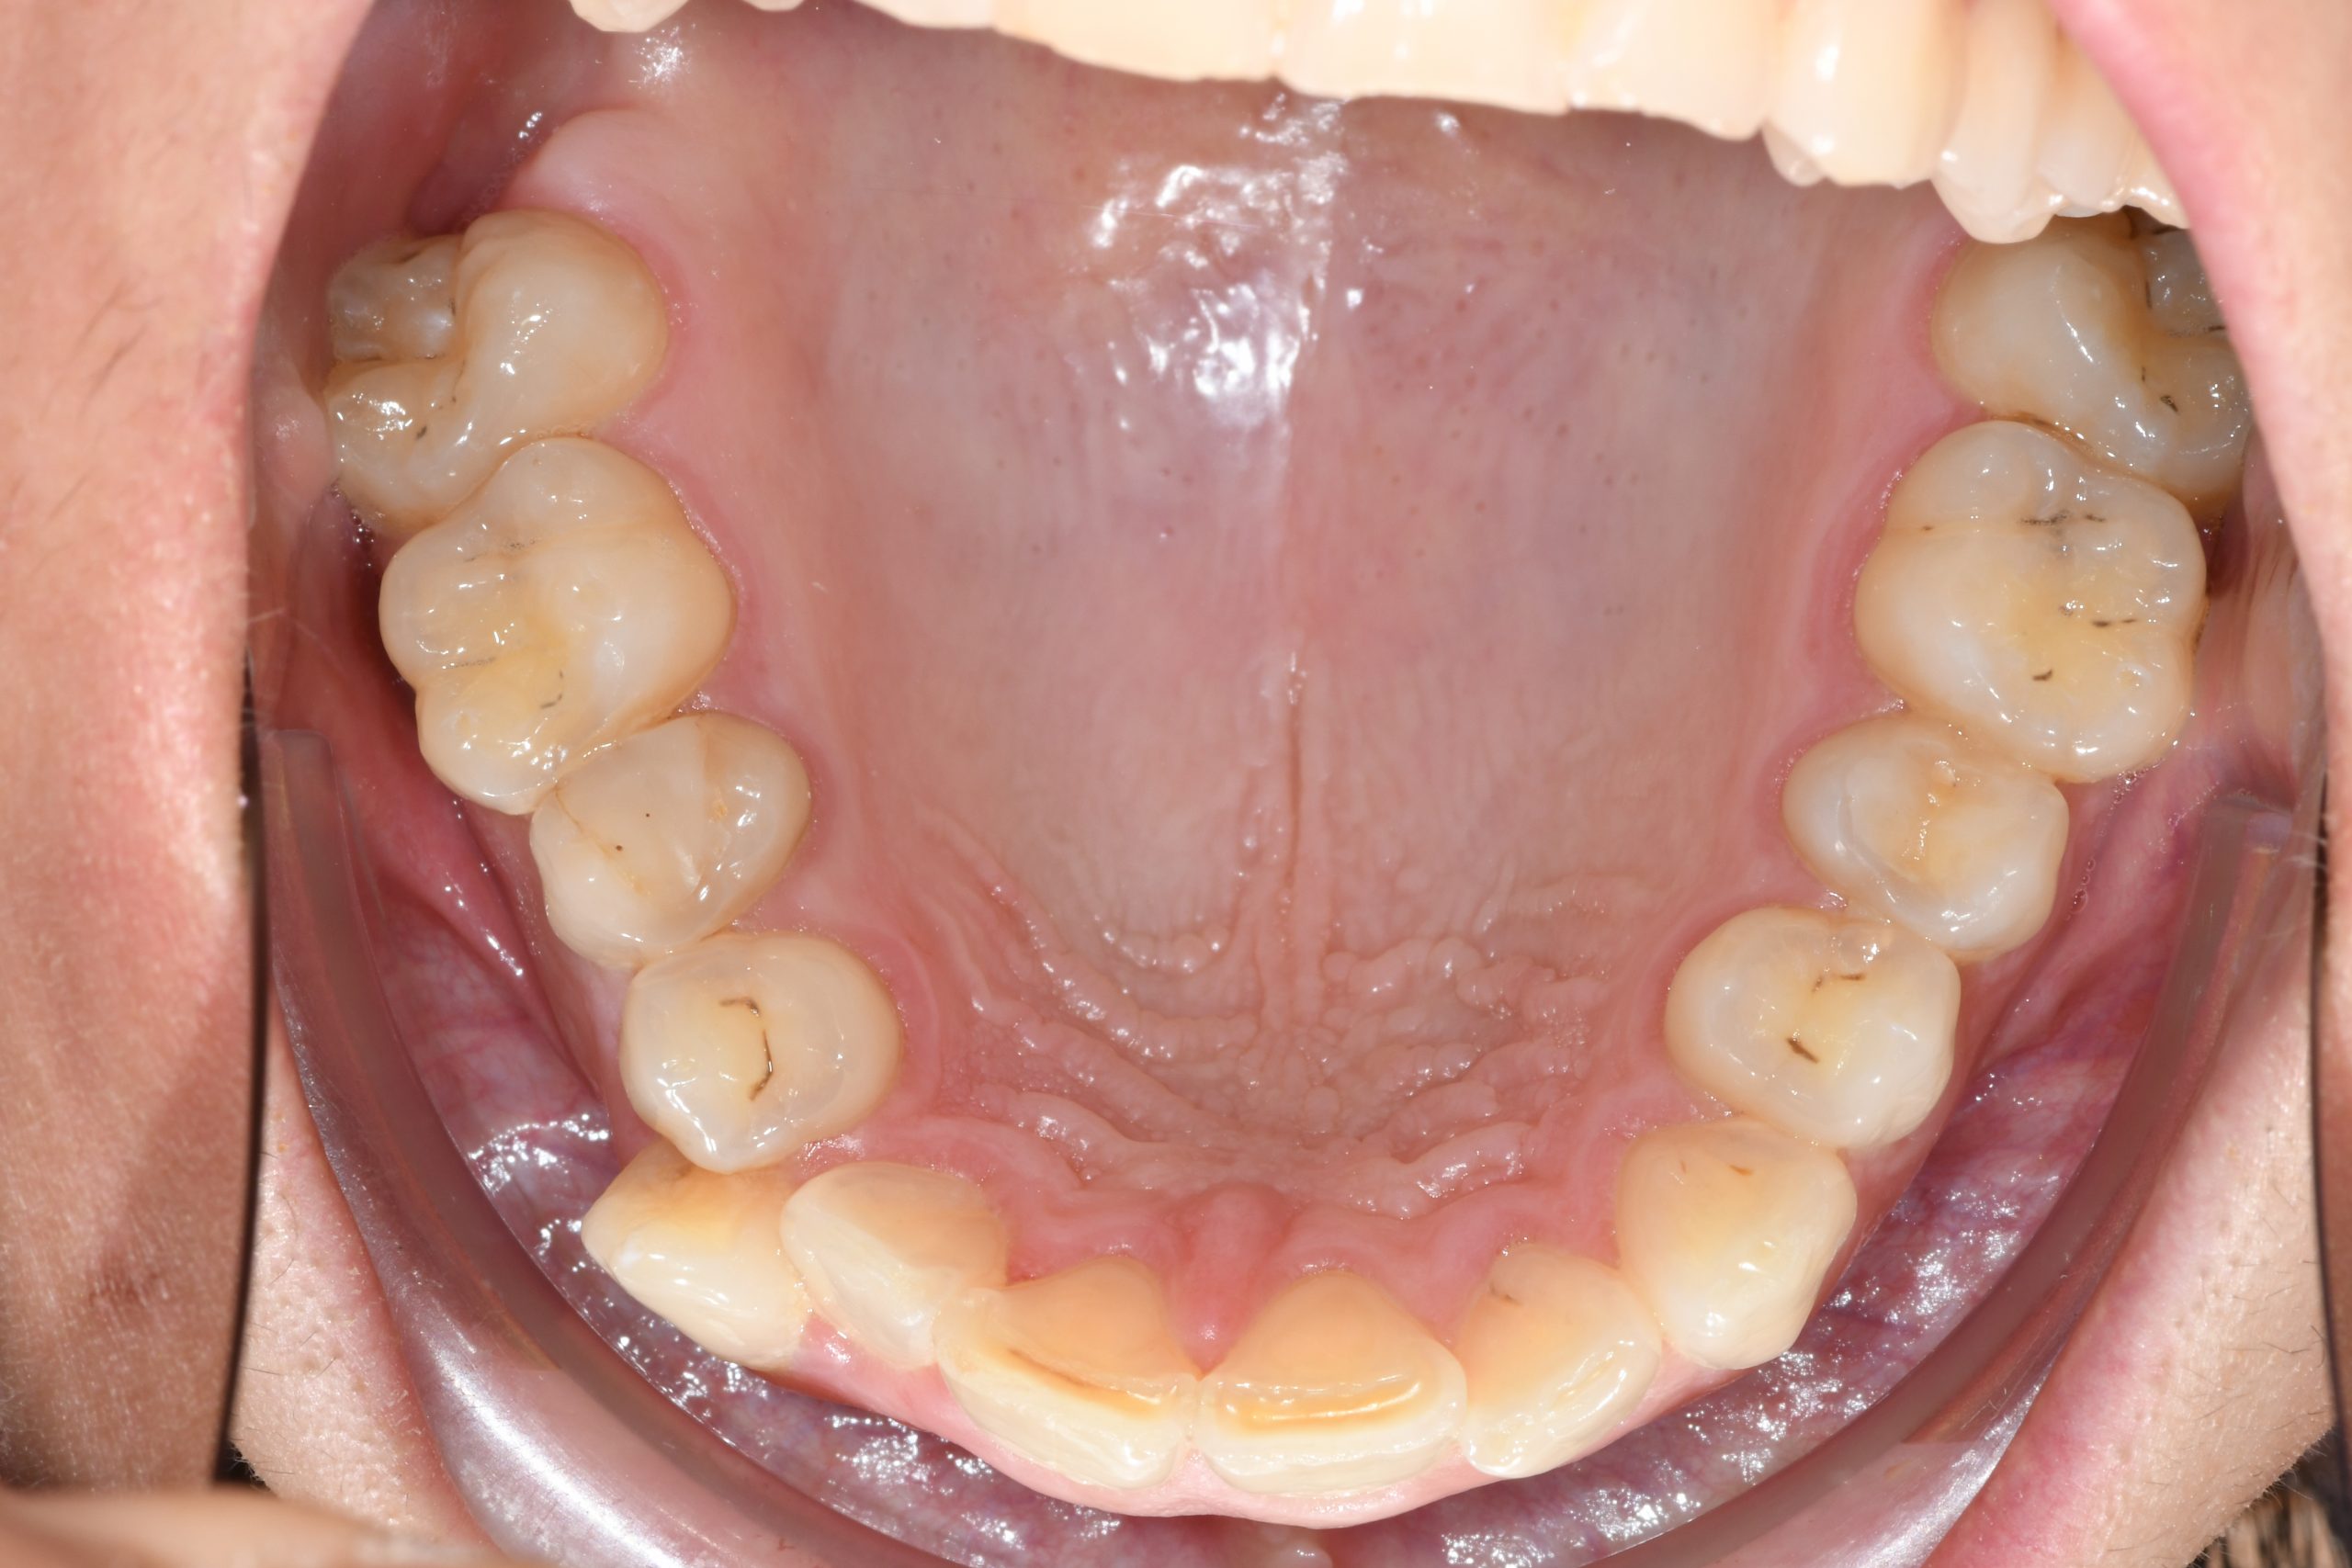

Az elmúlt évekből rengeteg szakmai referenciát tudnánk bemutatni, amelyek különböző fogszabályozási problémákat oldottak meg. Válogatva a több száz esetből, ezen az oldalon olyan képeket, információkat igyekeztünk bemutatni, amelyeknek a segítségével a jövőbeni pácienseinknek azt tudjuk üzenni: A Te fogsorod is lehet gyönyörű!

(Képeket a Pácienseink külön írásos beleegyezésével mutatjuk be!)